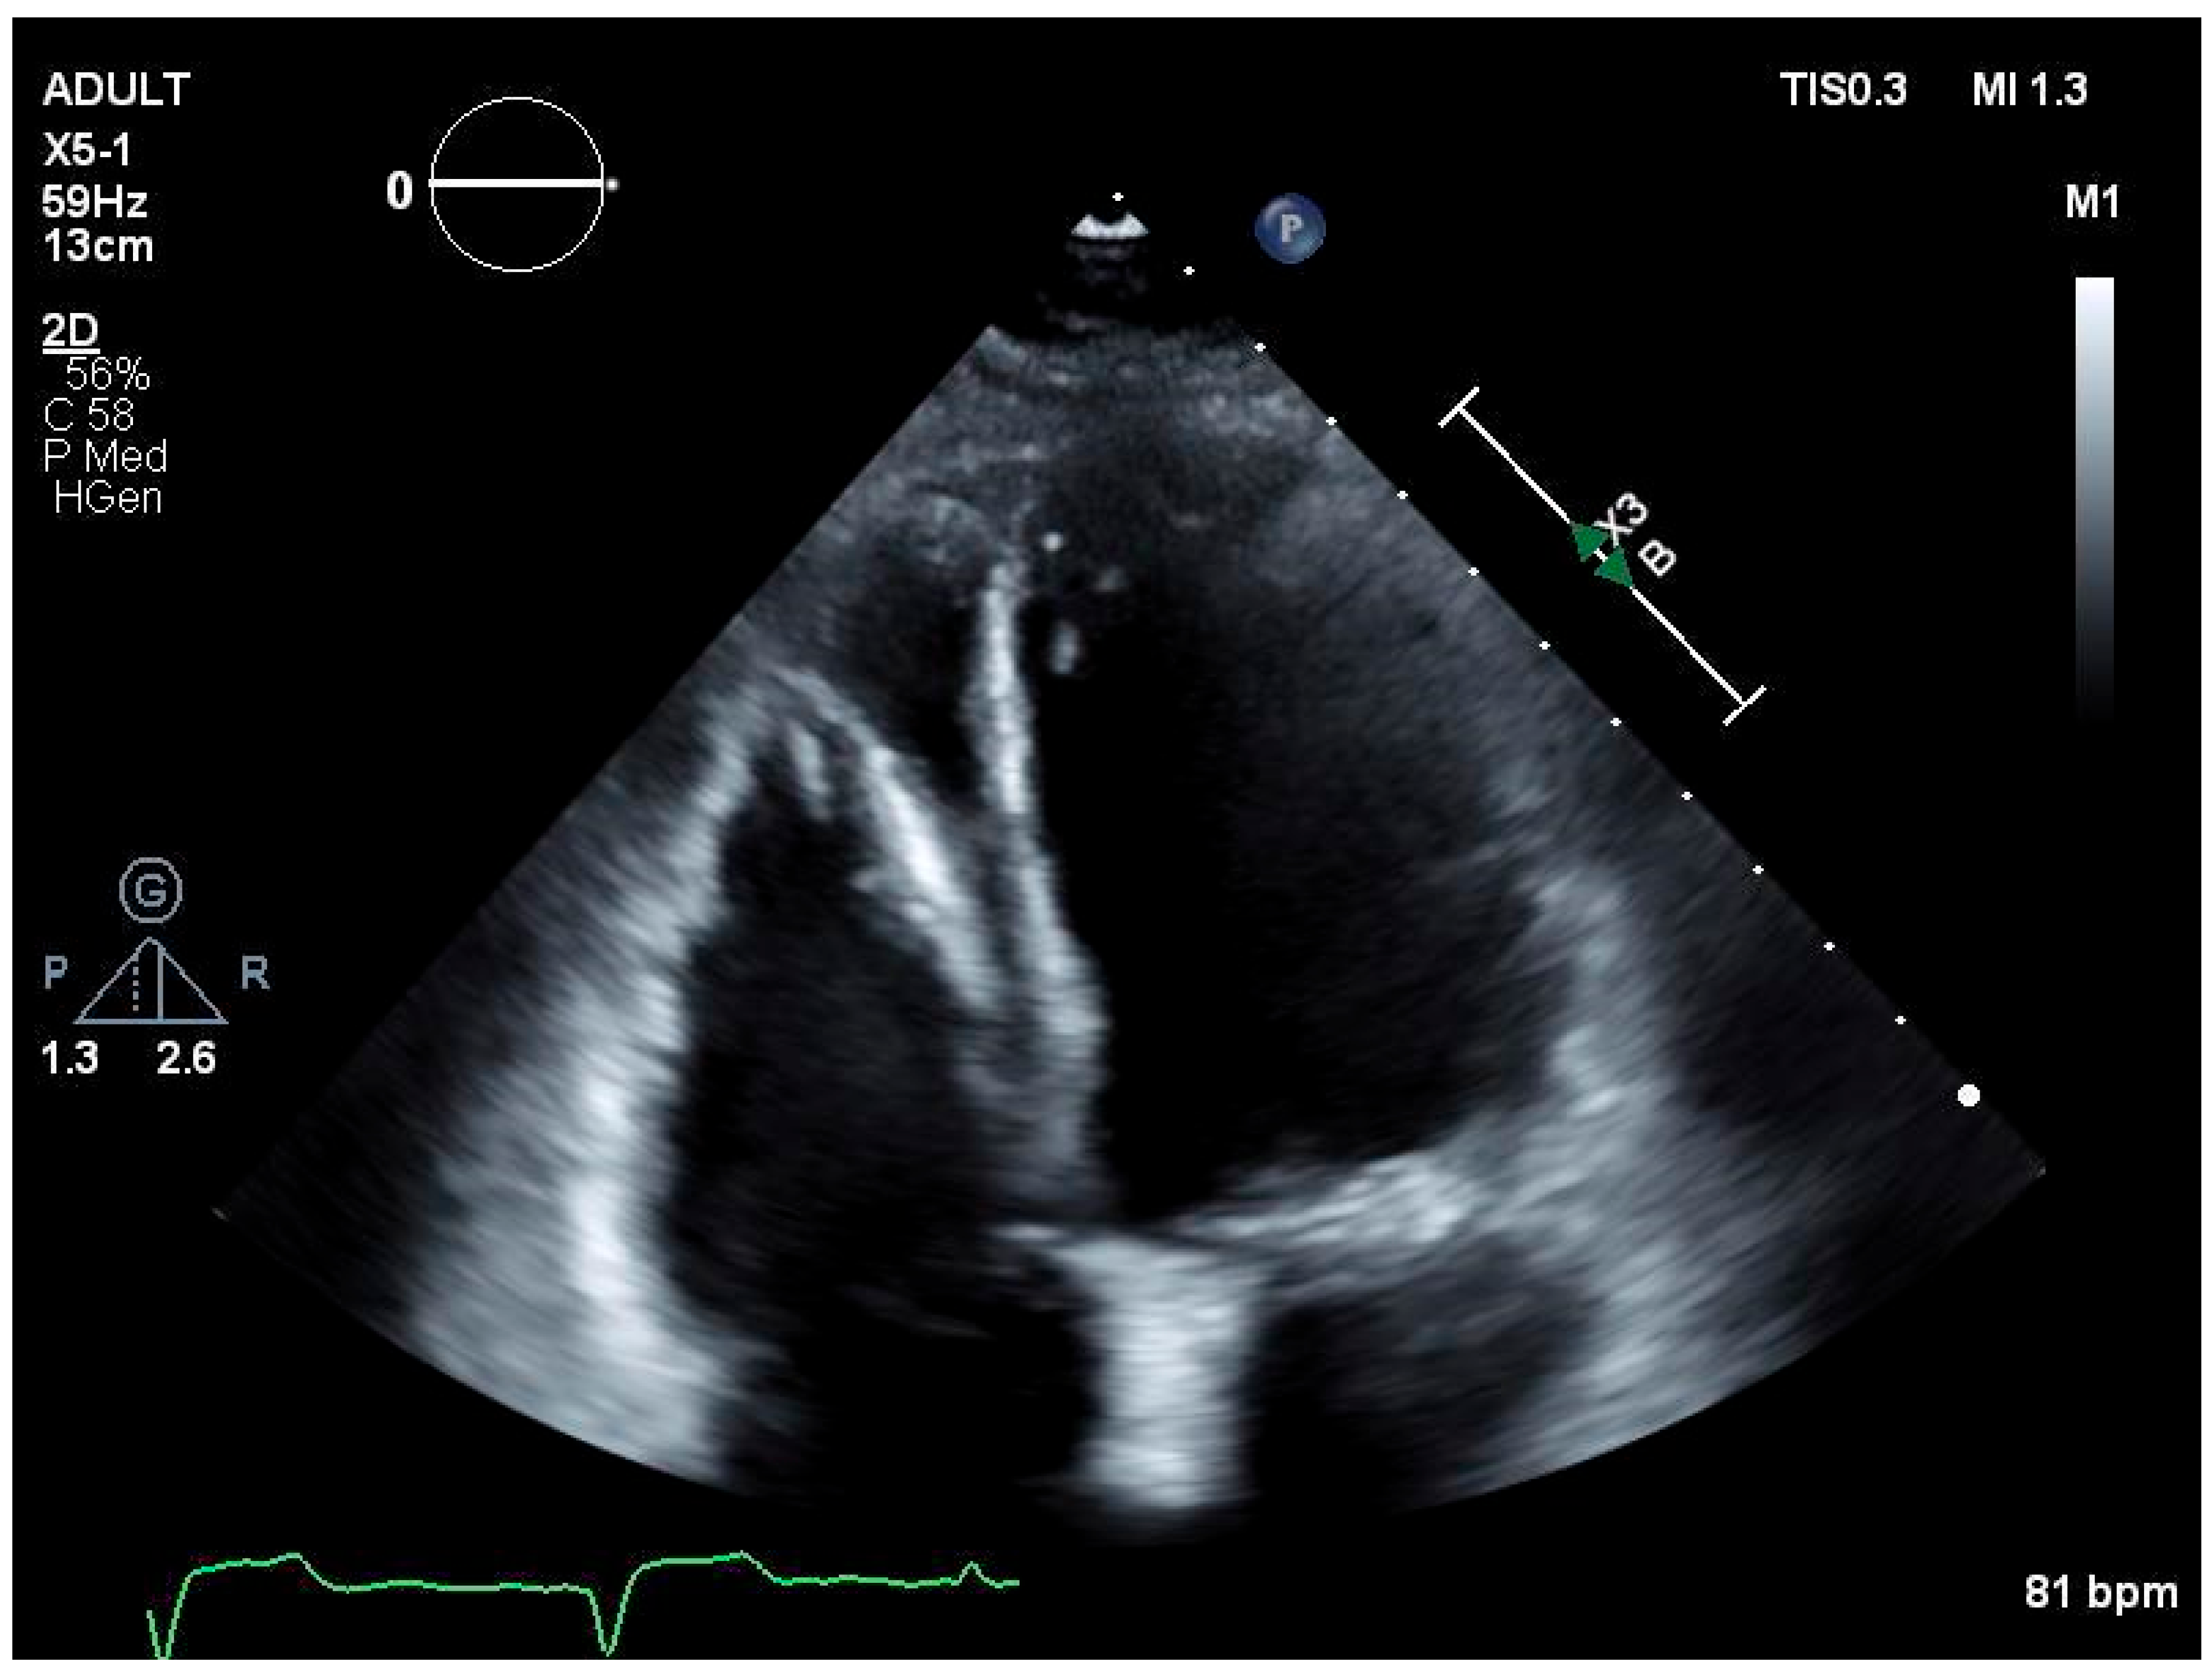

2. Clinical Presentation

2.1. Case History and Examination/Investigations